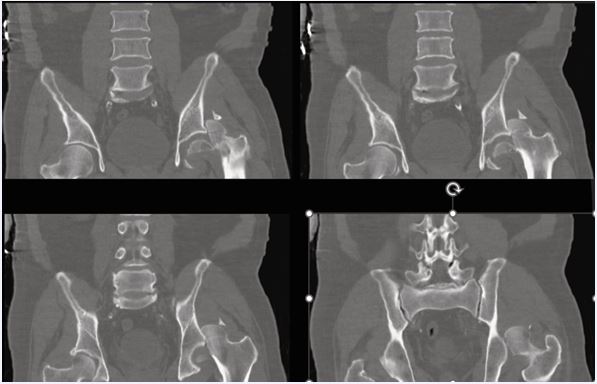

Given early hypercoagulability after head injury, we used an imaging-plus-hemostasis dual threshold to initiate prophylaxis once serial head CTs were stable and coagulopathy acceptable. Trauma and neurocritical-care guidance support starting LMWH/UFH within 24–72?h in appropriately selected TBI patients [11,14,15]. In a 4,951-patient multicenter cohort, each day of delay was associated with an 8% increase in VTE odds, and initiating >72?h after injury carried an ≈4-fold higher VTE risk compared with earlier start, without an increase in mortality [16,17]. Operationally, these data argue against deferral beyond the early window when imaging is stable (Figure 1 and Figure 2).

https://www.jscimedcentral.com/public/assets/images/uploads/image-1766058425-1.JPG

Figure 1 Pre-operative pelvic CT (coronal reconstructions) Coronal CT demonstrating a femoral head fracture with associated acetabular rim fragment consistent with Pipkin IV.